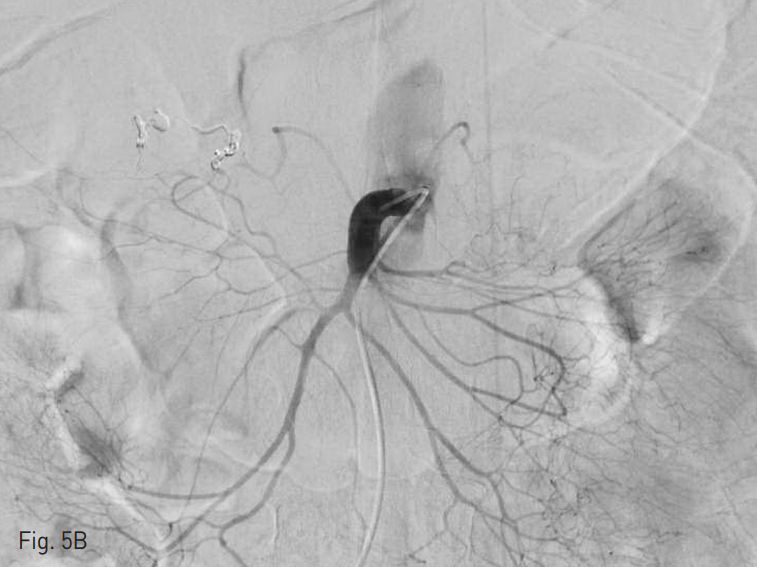

시술 중간 환자의 혈압이 떨어지기 시작하여 혈관외 유출이 있는 분지의 원위부인 위이자샘창자동맥(superior pancreaticoduodenal artery)을 microcoil 3개 (Tornado, Cook Medical, Bloomington, IN,USA)를 이용하여 막고 (Fig. 4) 근위부에서 n-butyl cyanoacrylate (NBCA; Histoacryl, B.Braun, Melsungen, Germany) + 요오드화 오일 (Lipiodol Ultra-Fluide, Guerbet, Paris, France)의 1:2.5 혼합액을 주사하여 샘창자상부동맥 (Supraduodenal artery)에 대한 색전술을 시행하였다.

Fig. 4

Three microcoils were placed at the distal branch of the superior pancreaticoduodenal artery.